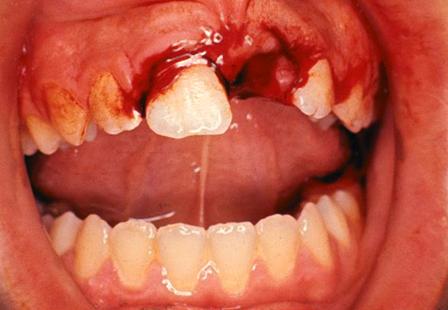

Self-induced soft tissue injury caused by lip and cheek-biting is an unfortunate complication of local anesthetic used in the mouth and is usually self-limiting and heals without complications, although bleeding may result. The frequency of self-induced soft tissue injury is higher when only one side is anesthetized. To help avoid the possibility of soft tissue injury, patients and their parents or caregivers need to be especially watchful and not allow the patient to bite, suck, or scratch on their lip, cheek, or tongue, and do not allow them to eat food while the anesthesia persists (still numb). If an injury does occur, it is best to cleanse the mouth with either OTC Peroxyl rinse, or warm salt water. If necessary, Tylenol or Motrin can be used to alleviate pain while the area is healing.